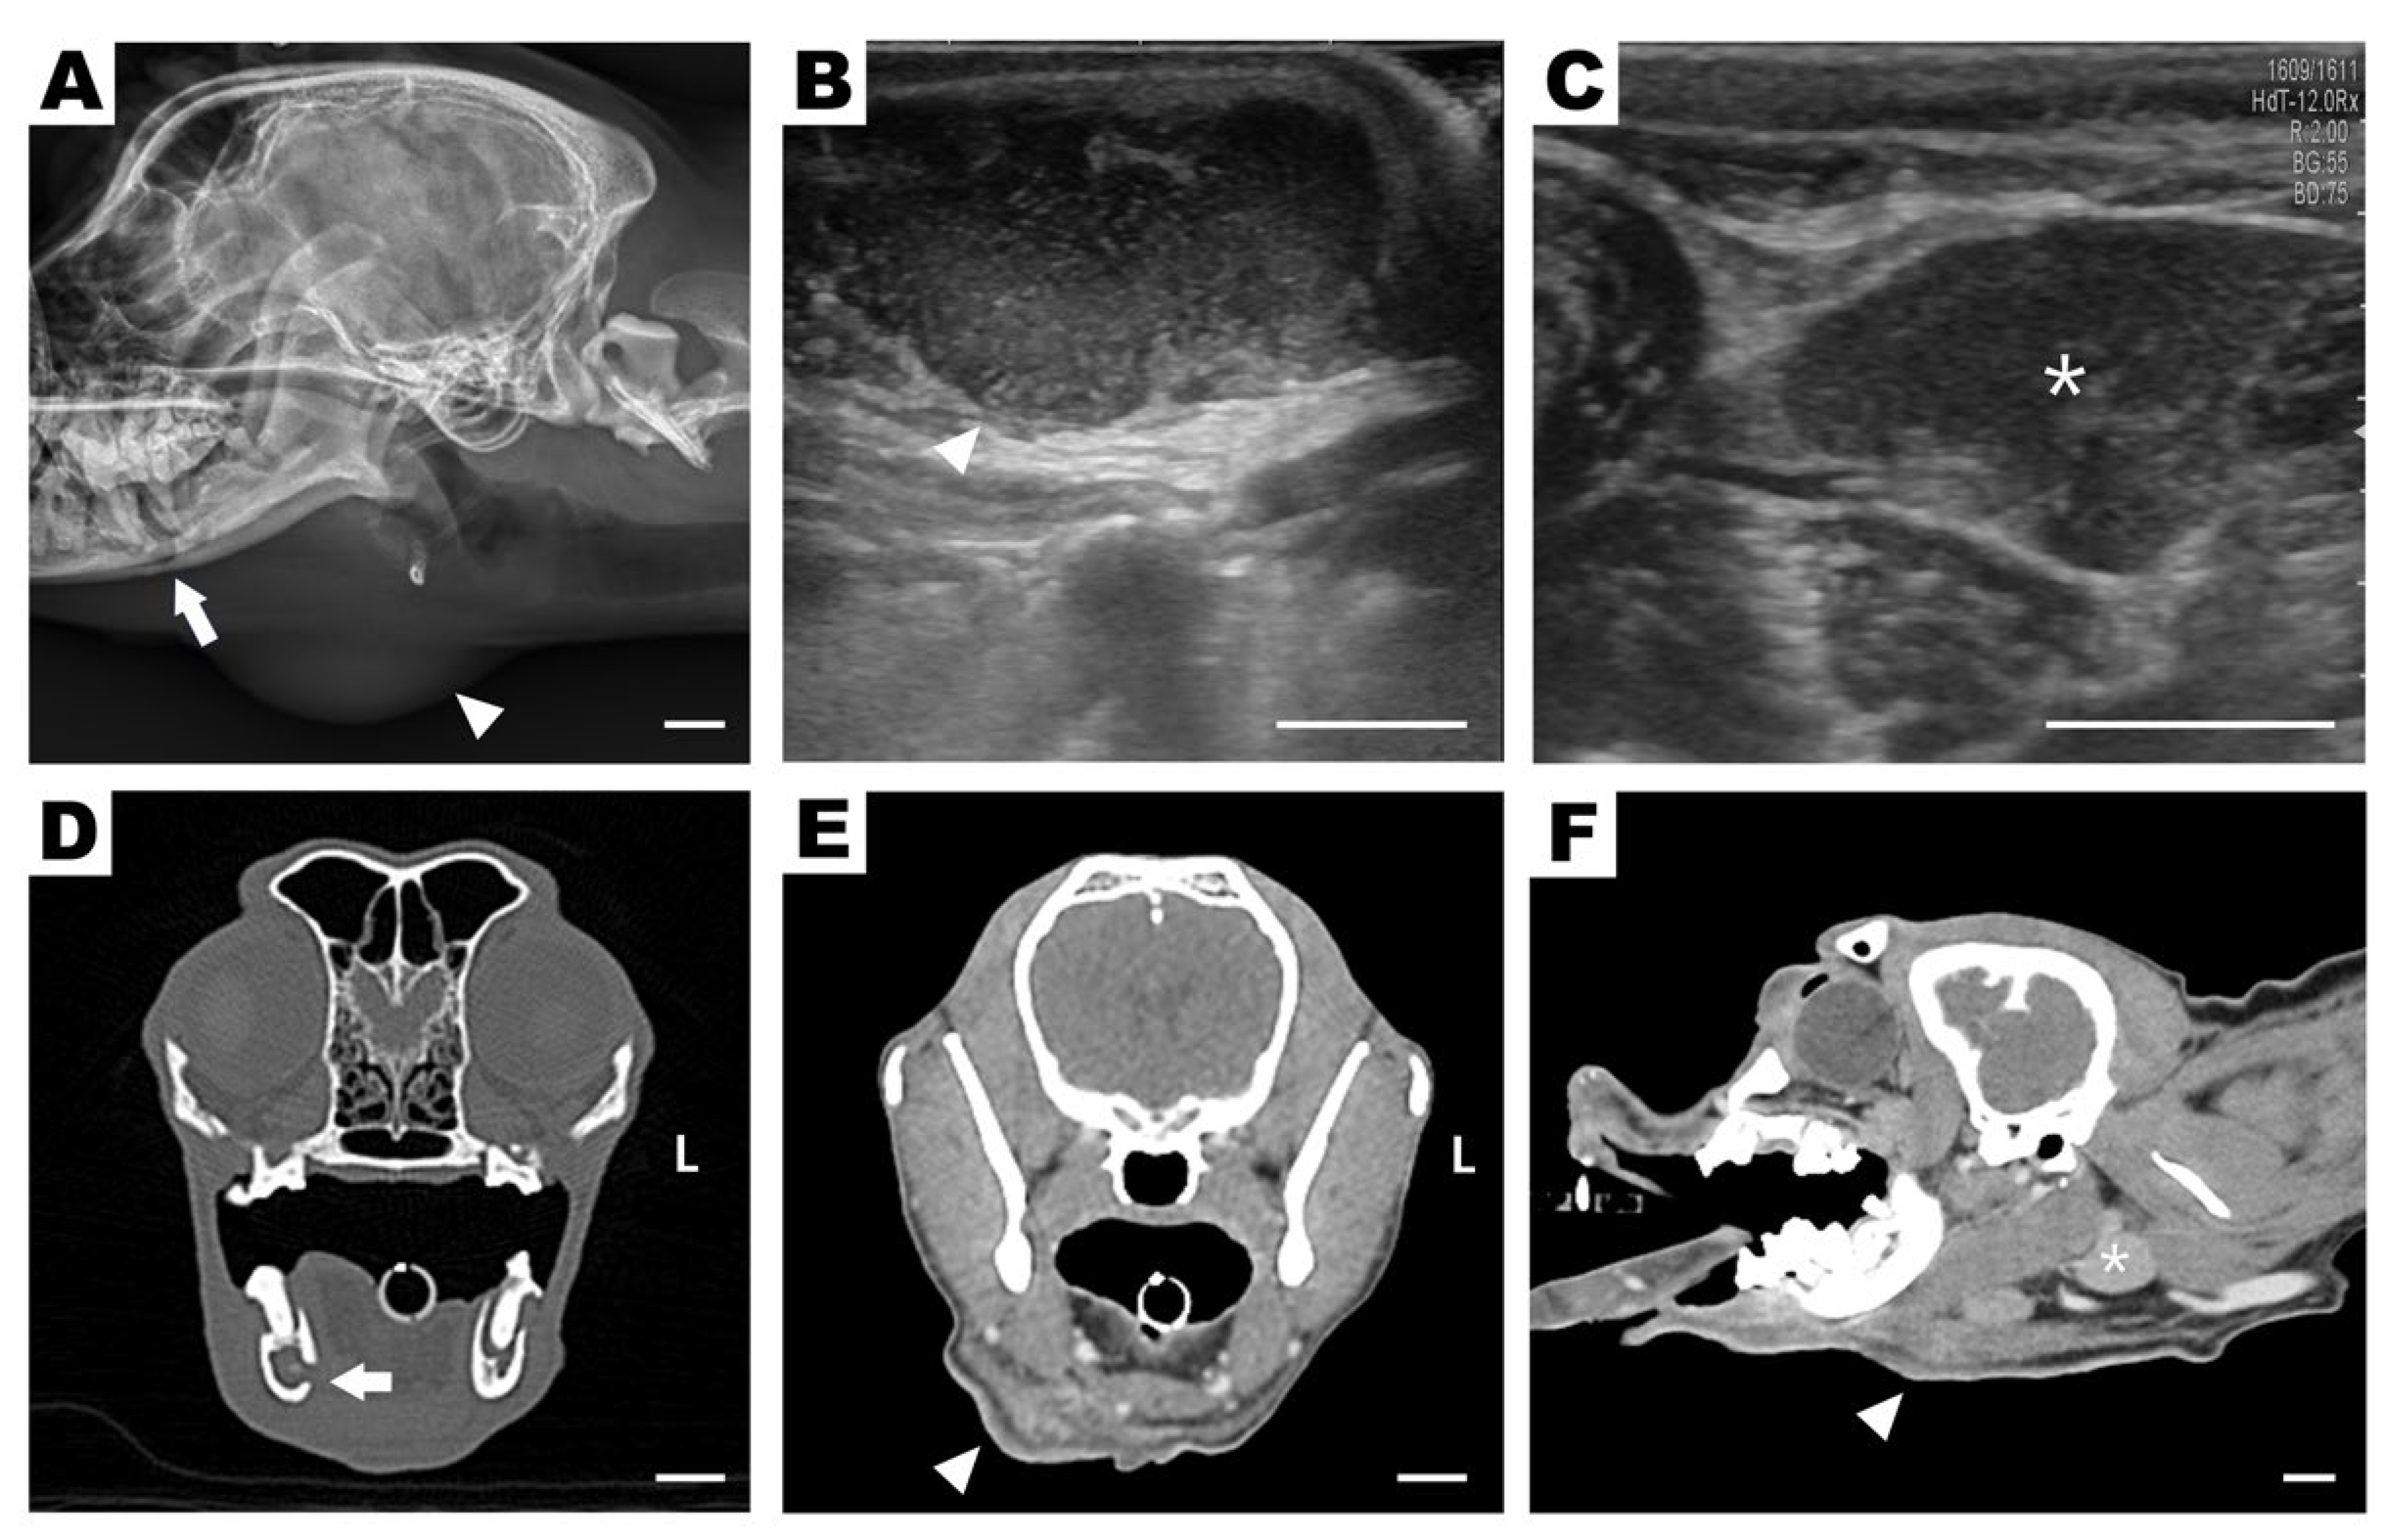

Lateral skull radiographs revealed alveolar bone lysis surrounding the right mandibular first molar (409) and an area of increased soft tissue opacity ventral to the angular process (Figure 2A). Ultrasonography revealed a cavitary, hypoechoic lesion in the subcutaneous region (Figure 2B), whereas a normal mandibular salivary gland echotexture without signs of ductal dilatation was observed (Figure 2C). A tubular hypoechoic structure cranial to the lesion was also observed, suggesting either a dilated salivary duct or a fistulous tract. Based on these findings, differential diagnoses included abscess, ruptured salivary duct, and salivary mucocele. On the day after admission, the subcutaneous lesion ruptured spontaneously, discharging purulent material externally and revealing a draining tract on the skin surface (Figure 1B). Further assessment using CT revealed discontinuity of the mandibular cortical bone adjacent to the mesial root of tooth 409, indicating infectious bone destruction (Figure 2D). A rim-enhancing, ill-defined cavitary lesion extending from the periapical area into the ipsilateral submandibular subcutaneous tissue was observed (Figure 2E,F), strongly suggestive of a draining fistulous tract of odontogenic origin.

Figure 2. Preoperative diagnostic imaging: radiography (A), ultrasonography (B,C), and computed tomography (CT) (DF). (A) Lateral skull radiograph obtained before abscess rupture, showing alveolar bone lysis around the right mandibular first molar (409) (white arrow) and a soft tissue opacity ventral to the mandibular angle (arrowhead), suggestive of a submandibular lesion. (B) Longitudinal ultrasound image of the submandibular region showing a cavitary, hypoechoic lesion (arrowhead). (C) Transverse ultrasound of the right mandibular salivary gland with preserved echotexture and no ductal dilation (asterisk). (D) Post-rupture transverse CT image at the level of the right mandibular first molar showing cortical bone discontinuity (arrow) due to periapical lysis. (E,F) CT images showing an enhancing, cavitary tract breaching the mandibular cortex and extending into the submandibular tissue (arrowhead), consistent with an external draining fistula. The right mandibular salivary gland appears unaffected (asterisk). Scale bars = 10 mm.